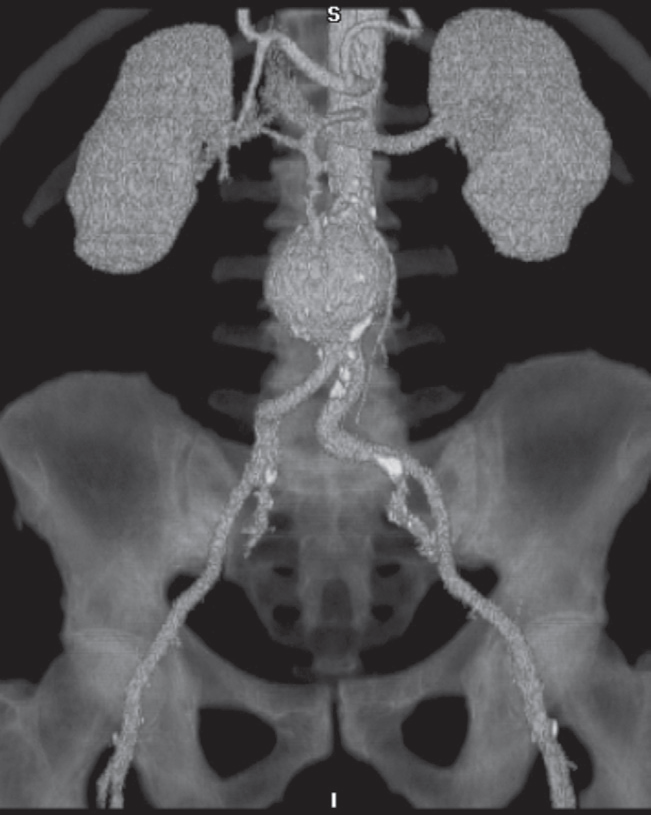

CT angiography

Rapid intravenous injections of contrast media result in significant opacification of blood vessels, which, with multiplanar or 3D reconstructions, can be exploited to produce angiograms. CT angiogram. Reconstruction from many thin axial sections following an intravenous injection of contrast demonstrating an aortic aneurysm Z . Calcification is seen in the wall of the arteries